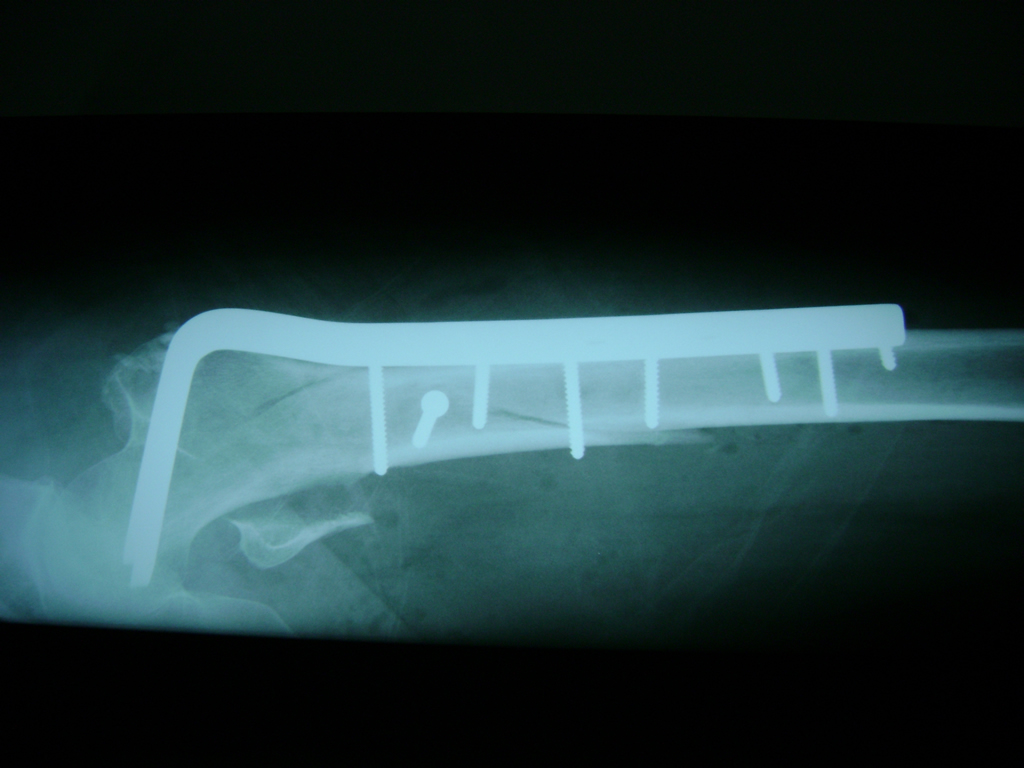

La cirugía de fractura de cadera se realiza para reparar una ruptura en la parte superior del hueso del muslo. Este hueso se denomina fémur.

Es parte de la articulación coxofemoral. Si una fractura de cadera no recibe tratamiento, es posible que deba permanecer en una silla o en la cama.

Esto puede llevar a otros problemas de salud potencialmente mortales, sobre todo si usted es una persona mayor.

A menudo se recomienda la cirugía para reparar la fractura debido a dichos riesgos.